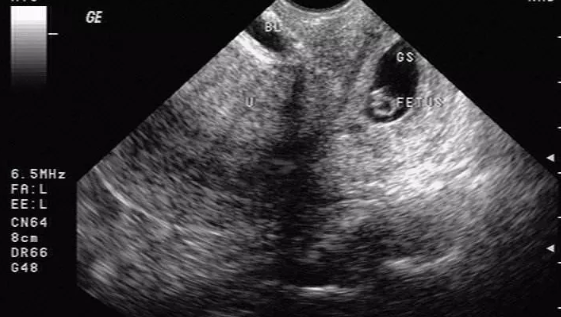

同時,患者需要進(jìn)行超聲檢查,超聲檢查是目前早期診斷宮頸妊娠最直接有效的首選方法。超聲檢查時宮頸管內(nèi)見妊娠囊影像,有時可見胚胎心管搏動。子宮體正常大小或稍大,宮腔內(nèi)無孕囊回聲;或者宮頸管內(nèi)見混合性包塊,與宮頸管肌壁間界限不清。但是宮頸妊娠主要需要與流產(chǎn)(難免流產(chǎn)、不全流產(chǎn)、先兆流產(chǎn))相鑒別。另外還需要與宮頸峽部妊娠、滋養(yǎng)細(xì)胞腫瘤、宮頸腫瘤性或炎癥性疾病相鑒別。